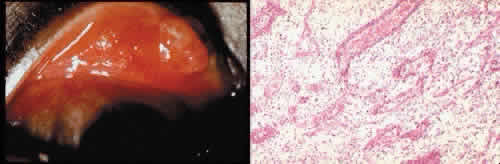

Retinal detachment (Fig. 42) occurs in approximately 2% to 8% of intracapsular cataract surgeries, compared with approximately 0.0013% in the general population. The incidence of retinal detachment after extracapsular cataract extraction and posterior chamber lens implantation ranges between 0.6% and 1.5%.121 Vitreous loss increases the incidence of postoperative detachments, particularly if there is vitreous incarceration into the cataract wound. The character of the retinal detachment is independent of the type of cataract surgery or the type of intraocular lens implanted. However, a lower incidence of proliferative vitreoretinopathy appears in cases of extracapsular cataract extraction than was formerly seen with intracapsular cataract extraction.

Fig. 42. Two cases of retinal detachment following cataract extraction. A. Retinal detachment was identified 4 weeks after cataract extraction. Fixed retinal folds indicate that the situation is inoperable, so no surgical repair was attempted. The anterior chamber angle has become occluded because of neovascularization associated with ischemic retina. B. Retinal detachment was identified 5 weeks after cataract extraction. Two attempts at surgical repair failed. The large equatorial cystic spaces indicated the presence of a scleral-buckling element. The actual material of the sponge and buckle has been lost during tissue processing. The cystic nature of the detached retinal tissue indicates that there was an extended time between the last retinal reattachment attempt and enucleation. In this case, peripheral anterior synechiae are present. The indication for enucleation was most likely a blind painful eye due to secondary glaucoma and reactive uveitis. (Hematoxylin-eosin stain; × 3.)